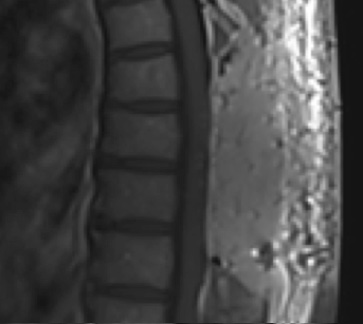

Preoperative MRI T2 demonstrating obstruction of CSF around the cord (blue arrow), resulting from the tumor (red arrow)